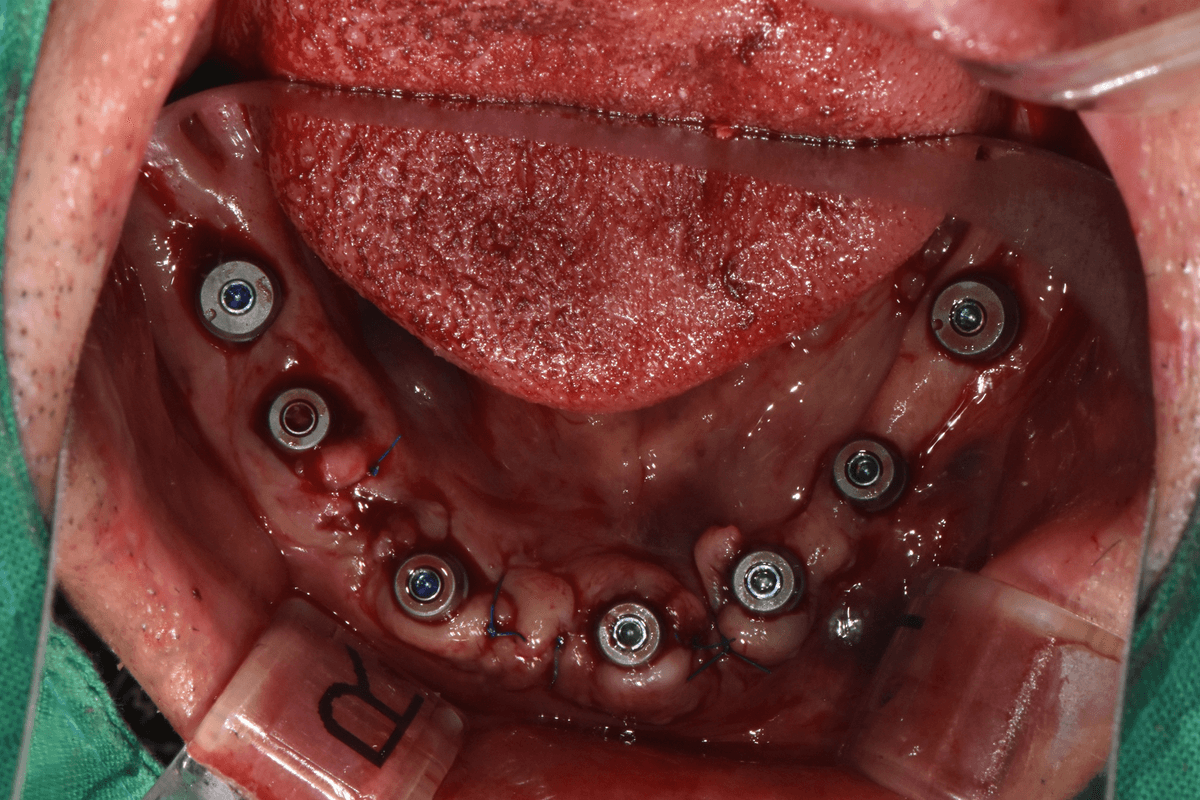

Implant không lật vạt &

Cấy ghép trong ngày

Không rạch nướu giúp giảm đau, giảm sưng và hồi phục nhanh hơn.

Ngay sau phẫu thuật Implant không lật vạt

Cấy ghép qua một lỗ nhỏ không cần rạch nướu,

giúp chảy máu và sưng tấy ở mức tối thiểu.

- • Cấy ghép qua lỗ nhỏ không cần rạch

- • Giảm thiểu chảy máu, đau và sưng

- • Trở lại sinh hoạt bình thường nhanh chóng

- • Cấy ghép Implant đồng thời với việc nhổ răng

- • Giảm số lần đến khám và thời gian điều trị

- • Giảm thiểu tình trạng tiêu xương hàm

Tối thiểu số lượng Implant

Chỉ 6 trụ hàm trên và 4 trụ hàm dưới để cố định chắc chắn